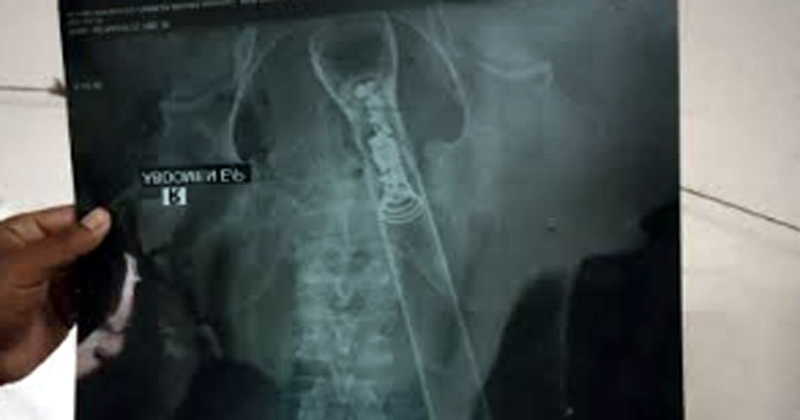

২৫০ শয্যা নোয়াখালী জেনারেল হাসপাতেল আবাসিক চিকিৎসা কর্মকর্তা সৈয়দ মহি উদ্দিন আবদুল আজিম জানান, পায়ু পথে টর্চলাইটসহ একজন বৃদ্ধ হাসপাতালে ভর্তি হয়েছিলো। হাসপাতালের জেনারেল সার্জন ডা. ফজলুর রহমান মানিকের নেতৃত্বে প্রায় দেড় ঘন্টা অস্ত্রপাচার চালিয়ে টর্চলাইটটি পায়ু পথ থেকে বের করা হয়। বর্তমানে রোগী হাসপাতালে চিকিৎসাধীন রয়েছে।